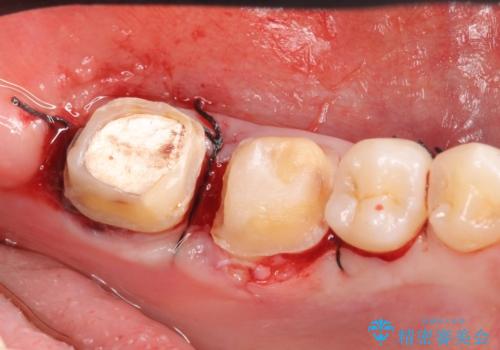

また左下6は遠心にあった歯茎より深い虫歯(縁下カリエス)の問題を解決するため、歯茎を下げる歯周外科手術を行いました。

歯周外科手術終了後、歯茎の回復を待ち左下6、7ともにオールセラミッククラウン(スタンダード)による補綴を行いました。

- オールセラミッククラウン…¥100,000×2、仮歯…¥10,000×2、歯冠長延長術…¥100,000費用は治療当時の料金となります